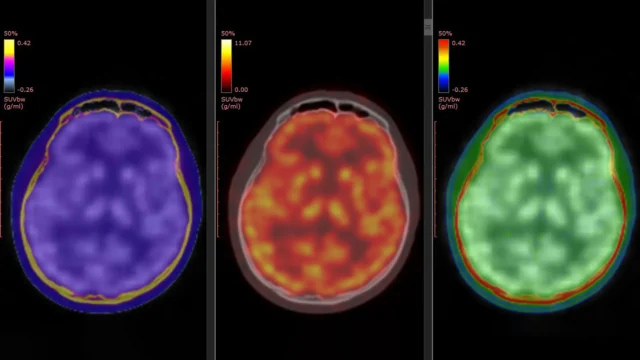

Um novo estudo publicado em Psiquiatria molecular Em 5 de março de 2026, ele tentou explicar esse mistério. O estudo foi liderado pelo professor Takuya Takahashi, do Departamento de Fisiologia da Escola Médica da Cidade de Yokohama, no Japão. A equipe usou uma técnica avançada de imagem de tomografia por emissão de pósitrons (PET) para observar diretamente as alterações no receptor de glutamato do ácido propiônico α-amino-3-hidroxi-5-marcado-4-isoxazol (AMPAR). Este receptor é uma proteína chave que ajuda a regular a comunicação entre as células cerebrais e desempenha um papel importante na plasticidade sináptica e na sinalização glutamatérgica em pacientes que recebem cetamina.

O estudo contou com um traçador PET desenvolvido anteriormente pela equipe conhecido como (¹¹C)K-2. Este rastreador permite aos cientistas visualizar AMPARs na superfície das células diretamente no cérebro humano vivo. Estudos anteriores em laboratório e em animais demonstraram que os efeitos antidepressivos da cetamina estão relacionados à atividade AMPAR. Um novo estudo fornece a primeira evidência direta de que esse processo ocorre em humanos.

Os pacientes receberam cetamina intravenosa ou placebo por duas semanas. Imagens PET do cérebro foram realizadas antes do tratamento e novamente após a última infusão. Esta abordagem permitiu aos pesquisadores comparar as mudanças no nível e distribuição de AMPARs no cérebro ao longo do tempo.

A cetamina não produziu mudanças uniformes em todo o cérebro. Em vez disso, as melhorias nos sintomas depressivos foram associadas a ajustes dinâmicos específicos da região nos níveis de AMPAR. Algumas áreas do córtex cerebral apresentaram aumento da densidade de receptores, enquanto áreas associadas ao processamento de recompensas, especialmente a habênula, apresentaram diminuição. Estas mudanças regionais estiveram intimamente associadas à melhoria dos sintomas depressivos dos pacientes.

“O efeito antidepressivo da cetamina em pacientes com DRT é mediado por mudanças dinâmicas nos AMPARs no cérebro humano vivo”, explicou o professor Takahashi. “Usando um novo rastreador PET, (11C)K-2, conseguimos visualizar como a cetamina altera a distribuição de AMPARs em regiões específicas do cérebro e como essas alterações se correlacionam com a melhora dos sintomas depressivos.”